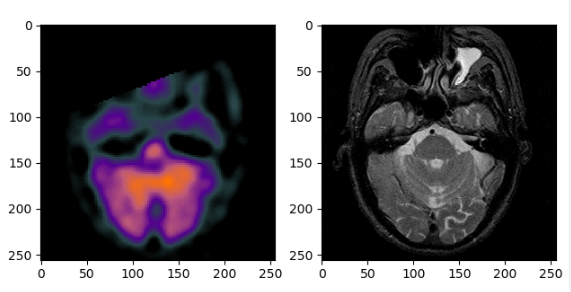

4 scipy.misc

from scipy.misc import imread

spect = imread(file_name1)

mri = imread(file_name2)

import matplotlib.pyplot as plt

fig=plt.figure()

f1 = fig.add_subplot(121)

f2 = fig.add_subplot(122)

f1.imshow(spect)

f2.imshow(mri,cmap='gray') # 注:单通道灰度图必须加上cmap='gray'才能正确显示

plt.show()